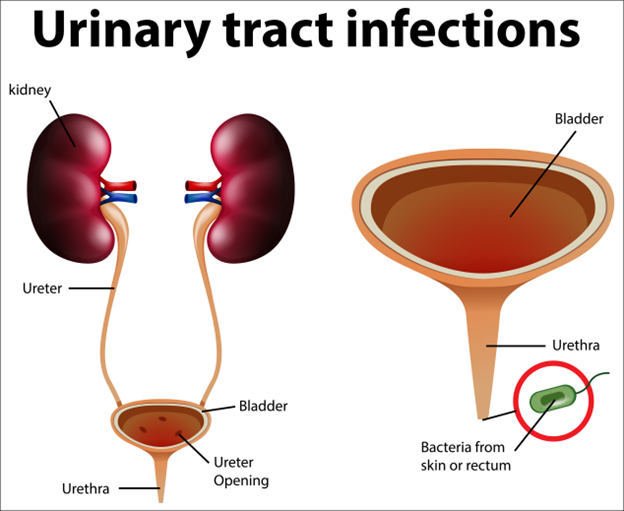

Recurrent UTIs: When It Could be a Chronic UTI

Urinary tract infections (UTIs) are a common health problem, affecting millions of people every year. While most UTIs are acute and can be treated with

A Closer Look at Chronic Urinary Tract Infection (UTI)

A chronic or persistent urinary tract infection is an ongoing infection of the urinary tract for a prolonged period despite treatment. The infection may recur